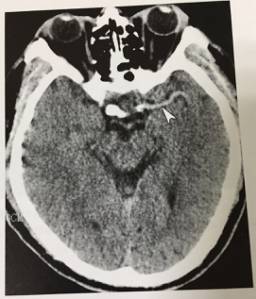

2、大脑中动脉“高密度”征

患者右侧偏瘫3小时,CT平扫示左侧大脑中动脉密度增高(无尾白箭头)脑实质未见异常,MRI证实为左侧大脑中动脉血栓形成。